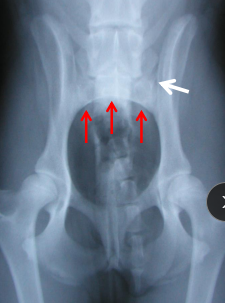

Pelvis Fractures

Considerations: Multi physes, normally breaks at multi sites

Sciatic n.: through ischiatic notch

Weight transfer: paw → tibia → femur → acetabulum → ilium → SI joint

Et: males > females, trama

Dt: Rads, CT for complex fractures/Sx planning

Tx:

Rx: non-displaced, unilateral, non-articular, non-weight-bearing fractures

6 w crate rest, sling, pain control, controlled walks, PT

Sx: ilium/acetabulum/SI joint (weight-bearing), bilateral fractures, displacement, colon compromise, pelvic canal compromise (parturition), sciatic entrapment

Ilium: plate + screws

Acetabulum: plate + screws, cross pins, PMMA

SI joint: screw stabilization